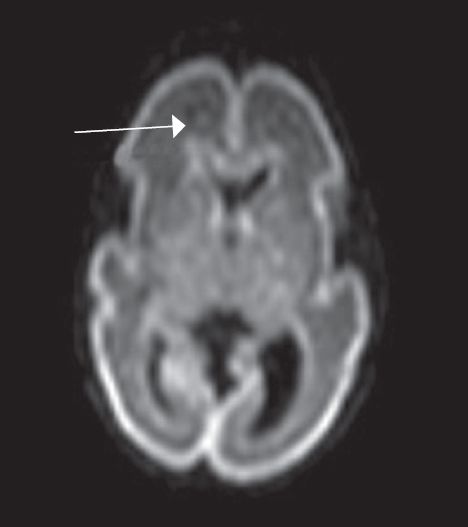

Как видно из таблицы, при выполнении МР-исследования в ПКВ 27–32 недели герминальный матрикс визуализировался у восьми недоношенных детей на ДВИ в виде усиления МР-сигнала вдоль боковых стенок боковых желудочков мозга, а также вдоль передних рогов над хвостатыми ядрами с обеих сторон (рис. 4). На Т2 ВИ герминальный матрикс достоверно выявлен у семи новорожденных (рис. 5). На Т1 ВИ герминальный матрикс достоверно выявлен у двух новорожденных (рис. 6). На последовательностях FLAIR герминальный матрикс не визуализировался.

Рис. 4. МРТ головного мозга недоношенного ребенка (ПКВ 28 недель), ДВИ, аксиальная проекция. Визуализируется гиперинтенсивный МР-сигнал от герминального матрикса в проекции наружных отделов боковых желудочков (отмечен стрелками)

Fig. 4. MRI of preterm newborn (PCA 28 wks.), DWI, axial plane. Hyperintensive MR-signal from the germinal matrix in the projection of the external parts of lateral ventricles (marked by arrows)